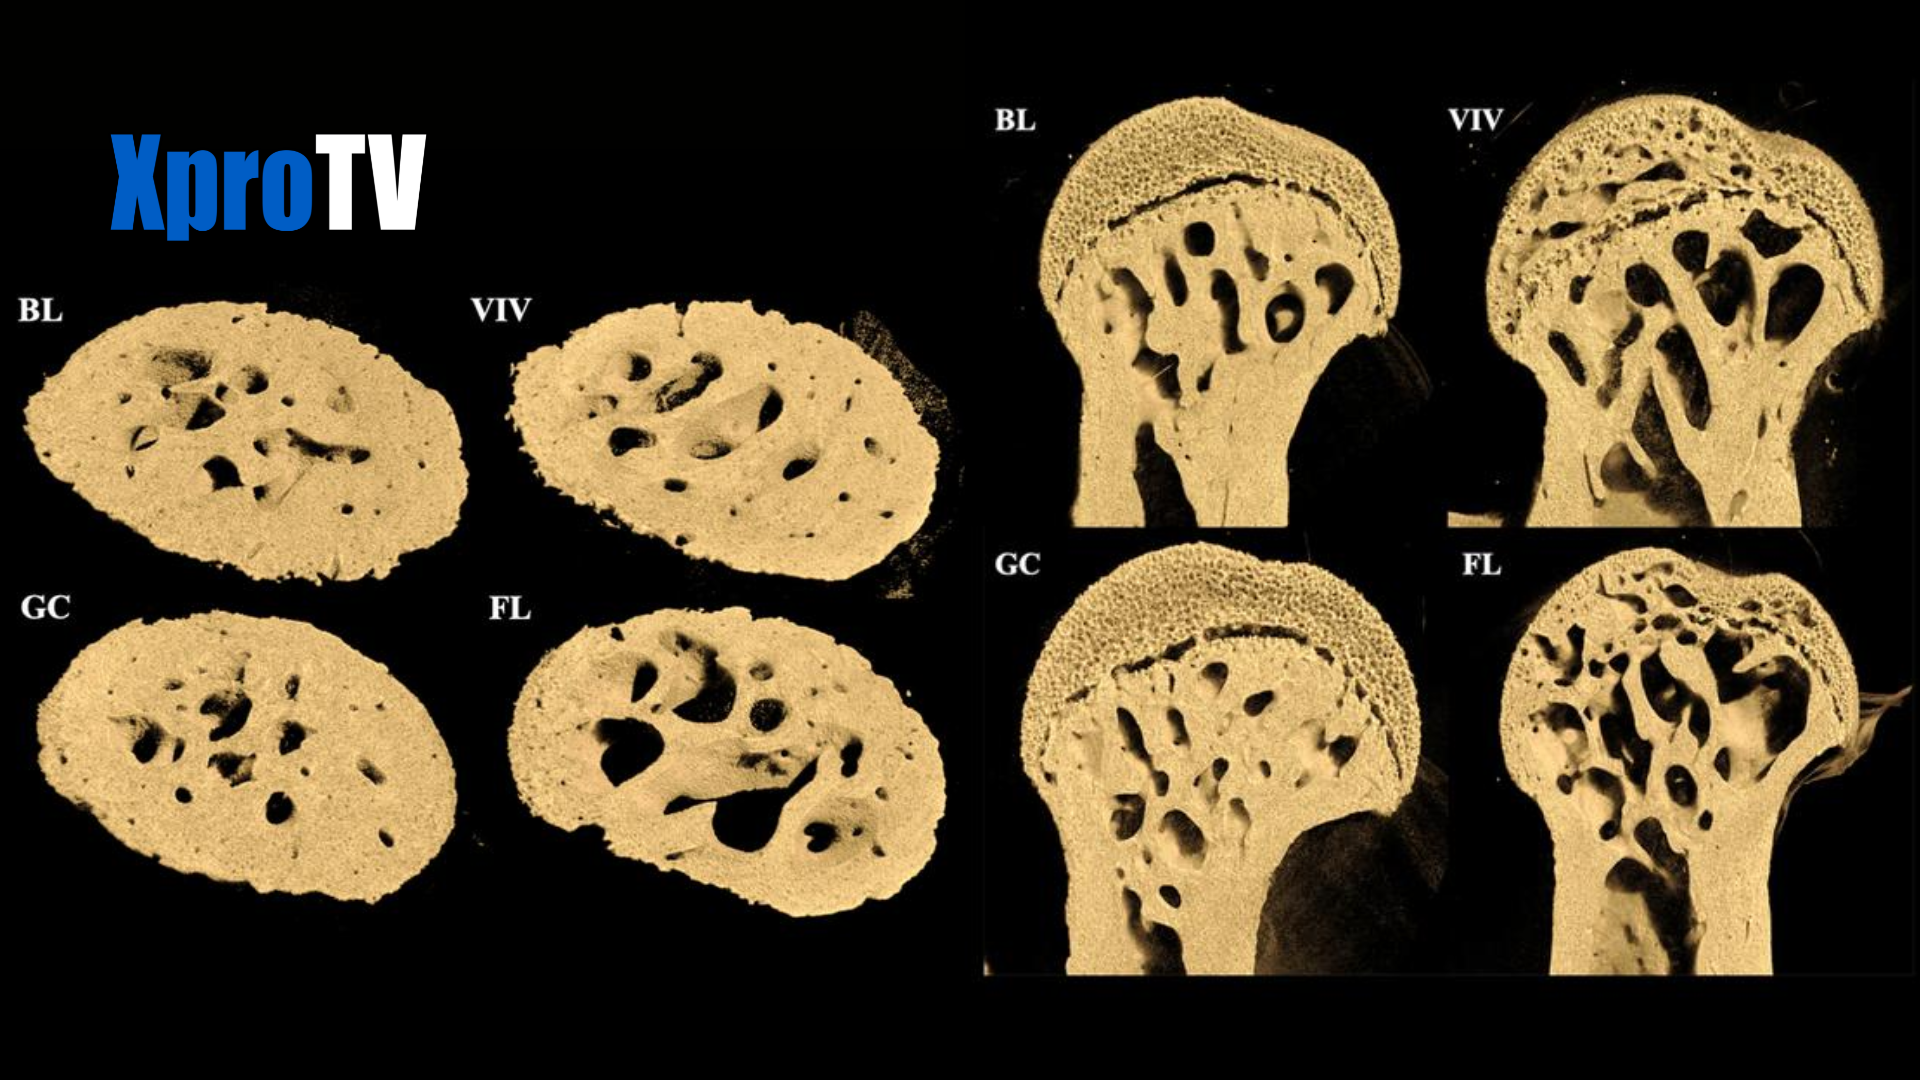

• Los huesos que normalmente soportan peso, como el fémur, sufrieron un grave deterioro.

• Aparecieron grandes agujeros en los extremos del fémur, cerca de las articulaciones de la cadera y rodilla.